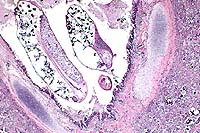

Signalment: 4-month-old, Berkshire, female, porcine.

History: Over a 2-to-3 week period approximately 28, 2- to 3-week-old piglets from the same pen died. A couple of pigs in the pen were coughing. This pig was sick for approximately 10 days and had a rough hair coat. The pig was given penicillin for a couple of days but did not improve.

Gross Pathology: This 8.6 kg, female Berkshire pig has fibrin and a congealed coagulum of red-tinged fluid on the pleural surface of the lungs and ribs, and fibrin on the serosal surface of the abdominal organs. The anteroventral aspect of the left and right cranial lung lobes are purple and firm, involving approximately 30% of both sides. There is fibrin adhered to 80% of the dorsal pleural surface of the lungs, with the greatest amount adhered to the anterior aspect. In the lumen of the trachea, extending down the bronchi, are numerous, thin, white, 2-6 cm long, nematode parasites consistent with Metastrongylus spp. There is a layer of fibrin adhered to the epicardial surface of the heart. There are greater than 50 ascarid parasites in the lumen of the distal esophagus, stomach, and small intestines. There are multiple, variably-sized white foci disseminated randomly on the serosal surface of the liver and throughout the parenchyma. There is a single ascarid parasite in the lumen of the bile duct extending into the gall bladder. All lymph nodes are prominent.

Contributor's Diagnosis and Comments: 1. Severe, subacute to chronic, lobular, eosinophilic, interstitial pneumonia and bronchiolitis with intrabronchiolar nematode parasites and intra-alveolar eggs containing larvae, lung. 2. Severe, subacute, fibrinous pleuritis, lung.

Metastrongylus is the only genus found in the family Metastrongylidae. All species are large white parasites of the bronchi and bronchioles of swine and the three most important species of this genus are M. apri, M. pudendotectus, and M. salmi. The intermediate host for these parasites is the earthworm. The oviparous females lay eggs containing the first stage larvae which are then passed in the feces of infected swine. The eggs do not hatch or develop into infective larvae unless they are ingested by an earthworm. In the earthworm, the larvae develop to the third, infective stage in approximately 10 days and remain quiescent unless the earthworm is eaten by a pig. Migration in the pig is through the lymphatics from the intestine to the lungs. In this case, the interstitial pneumonia and bronchiolitis in this pig may be the result of both the Metastrongylus parasites, as well as migration of Ascaris suum larvae due to the heavy ascarid load.

Nematode parasites found in the lungs of other mammalian species include:Dictyocaulus filaris (sheep, goats, other small ruminants), D. viviparous (cattle) and D. arnfieldi (horses, donkeys), Protostrongylus rufescens (sheep, goats, deer), Muellerius capillaris (sheep, goats), Crenosoma vulpis (foxes), Filaroides hirthi(dogs), Aelurostrongylus abstrusus (cats), and Angiostrongylus vasorum (dogs, foxes).